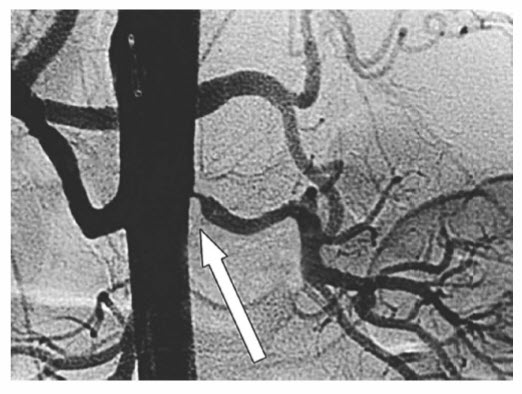

Approximately 80% of all renal artery occlusive lesions are caused by atherosclerosis, which typically involves a short segment of the renal artery ostia and represents spillover disease from a severely atheromatous aorta (Fig. below). Atherosclerotic lesions are bilateral in two-thirds of patients. Individuals with this disease commonly present during the sixth decade oflife. Men are affected twice as frequently as women. Atherosclerotic lesions in other territories such as the coronary, mesenteric, cerebrovascular, and peripheral arterial circulation are common. When a unilateral lesion is present, the disease process equally affects the right and left renal arteries. The second most common cause of renal artery stenosis is FMD, which accounts for 20% of cases and is most frequently encountered in young, often multiparous women. FMD of the renal artery represents a heterogeneous group of lesions that can produce histopathologic changes in the intima, media, or adventitia. The most common variety consists of medial fibroplasia, in which thickened fibromuscular ridges alternate with attenuated media producing the classic angiographic "string of beads" appearance. The cause of medial fibroplasia remains unclear. Most common theories involve a modification of arterial smooth muscle cells in response to estrogenic stimuli during the reproductive years, unusual traction forces on affected vessels, and mural ischemia from impairment of vasa vasorum blood flow. Fibromuscular hyperplasia usually affects the distal two thirds of the main renal artery, and the right renal artery is affected more frequently than the left. Other less common causes of renal artery stenosis include renal artery aneurysm (compressing the adjacent normal renal artery), arteriovenous malformations, neurofibromatosis, renal artery dissections, renal artery trauma, Takayasu arteritis, and renal arteriovenous fistula.

Occlusive disease of the renal artery typically involves the renal ostium (arrow), as a spill over plaque extension from aortic atherosclerosis.